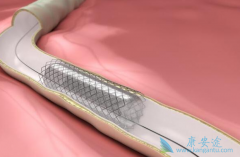

什么是 心脏支架手术 ?可以把心脏支架想象成是个细长的金属笼子,放在血管里就可以把即将堵死的血管撑开,心脏支架非常的细小,直径大约在2~4毫米,长几厘米,有空心、圆柱、网状金属管,一般都是用钛合金制成,是世界上最昂贵的一种金属。 心脏支 ...

不少人都听过心脏支架手术,这种手术堪称是当代心脏病学最伟大的一项发明。你知道这个小小的支架是怎么放到心脏里去的吗? 心脏支架 是通过介入手术的方式植入到人体的,我们可以从心脏介入手术可是说起,这样更好理解。心脏介入原理其实并不复杂。 ...

为了改善冠心病介入治疗短期和长期的疗效与安全性,所以研发了支架。第一代支架是金属裸支架,使冠心病介入治疗前进了一大步,使介入治疗变得非常安全,当血管发生严重狭窄时单纯球囊扩张预处理后,再用支架把血管完全撑开,就能解除心肌缺血危险,而且 ...

心脏支架 选哪种?放最好的支架?还是放最贵的支架?今天就给大家答疑解惑!心脏支架由具有强支撑力的合金制成,不同厂家支架的金属结构略有差别。心脏支架没有植入体内之前,包裹在球囊外面。植入时给球囊加压,支架打开至预定直径,使支架与血管壁完 ...